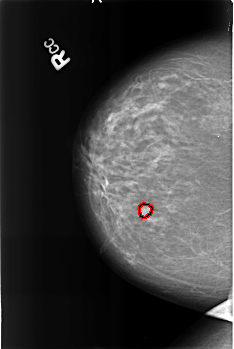

Digital Database for Screening Mammography

Volume: benign_04 Case: B-3356-1

B_3356_1.RIGHT_CC

RIGHT_CC LINES 4528 PIXELS_PER_LINE 3040 BITS_PER_PIXEL 12 RESOLUTION 50 OVERLAY

FILE: B_3356_1.RIGHT_CC.OVERLAY

TOTAL_ABNORMALITIES 1

ABNORMALITY 1

LESION_TYPE MASS SHAPE OVAL-LOBULATED MARGINS MICROLOBULATED

ASSESSMENT 4

SUBTLETY 4

PATHOLOGY BENIGN

TOTAL_OUTLINES 2